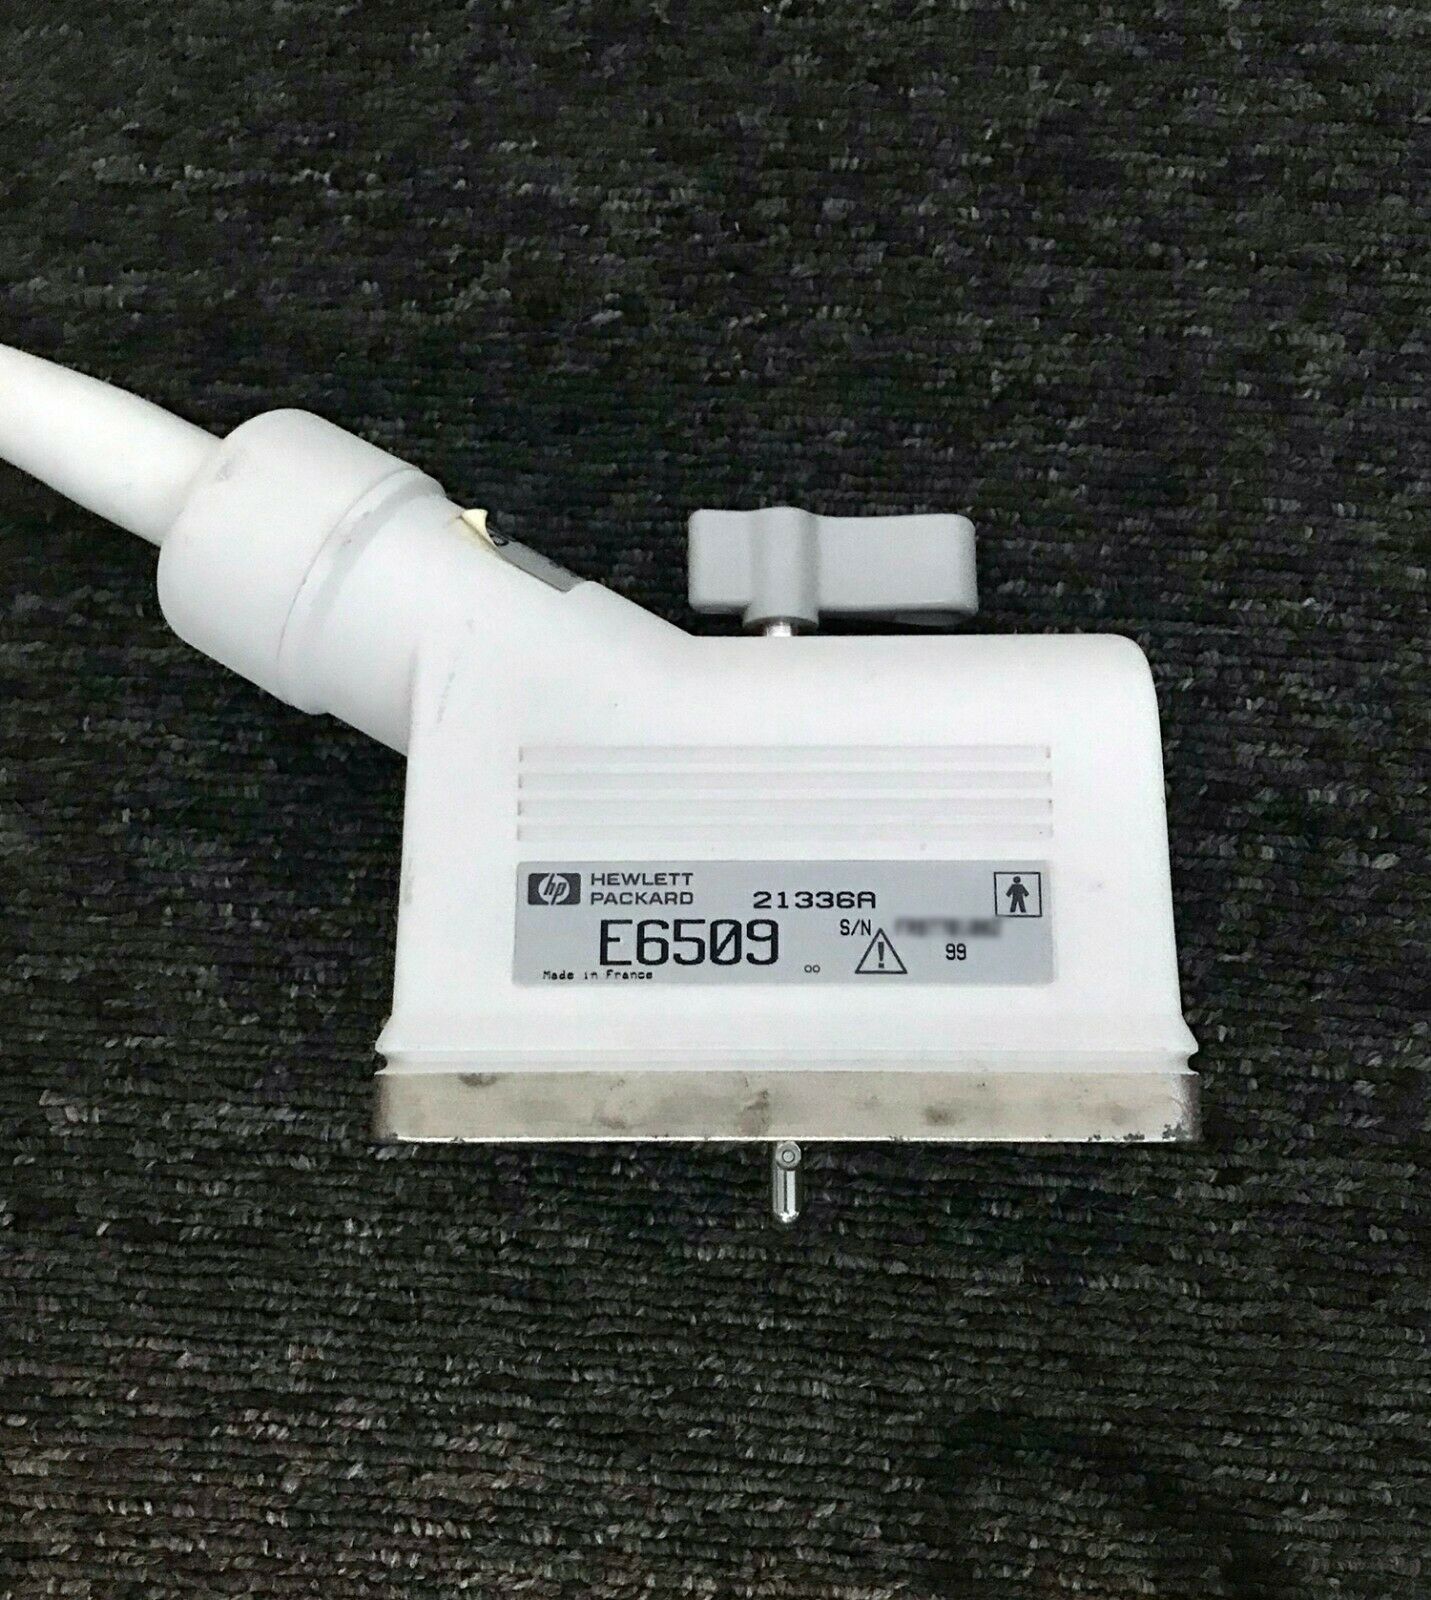

PHILIPS S12-4 ULTRASOUND TRANSDUCER PROBE

Sale price$ 4,305.00